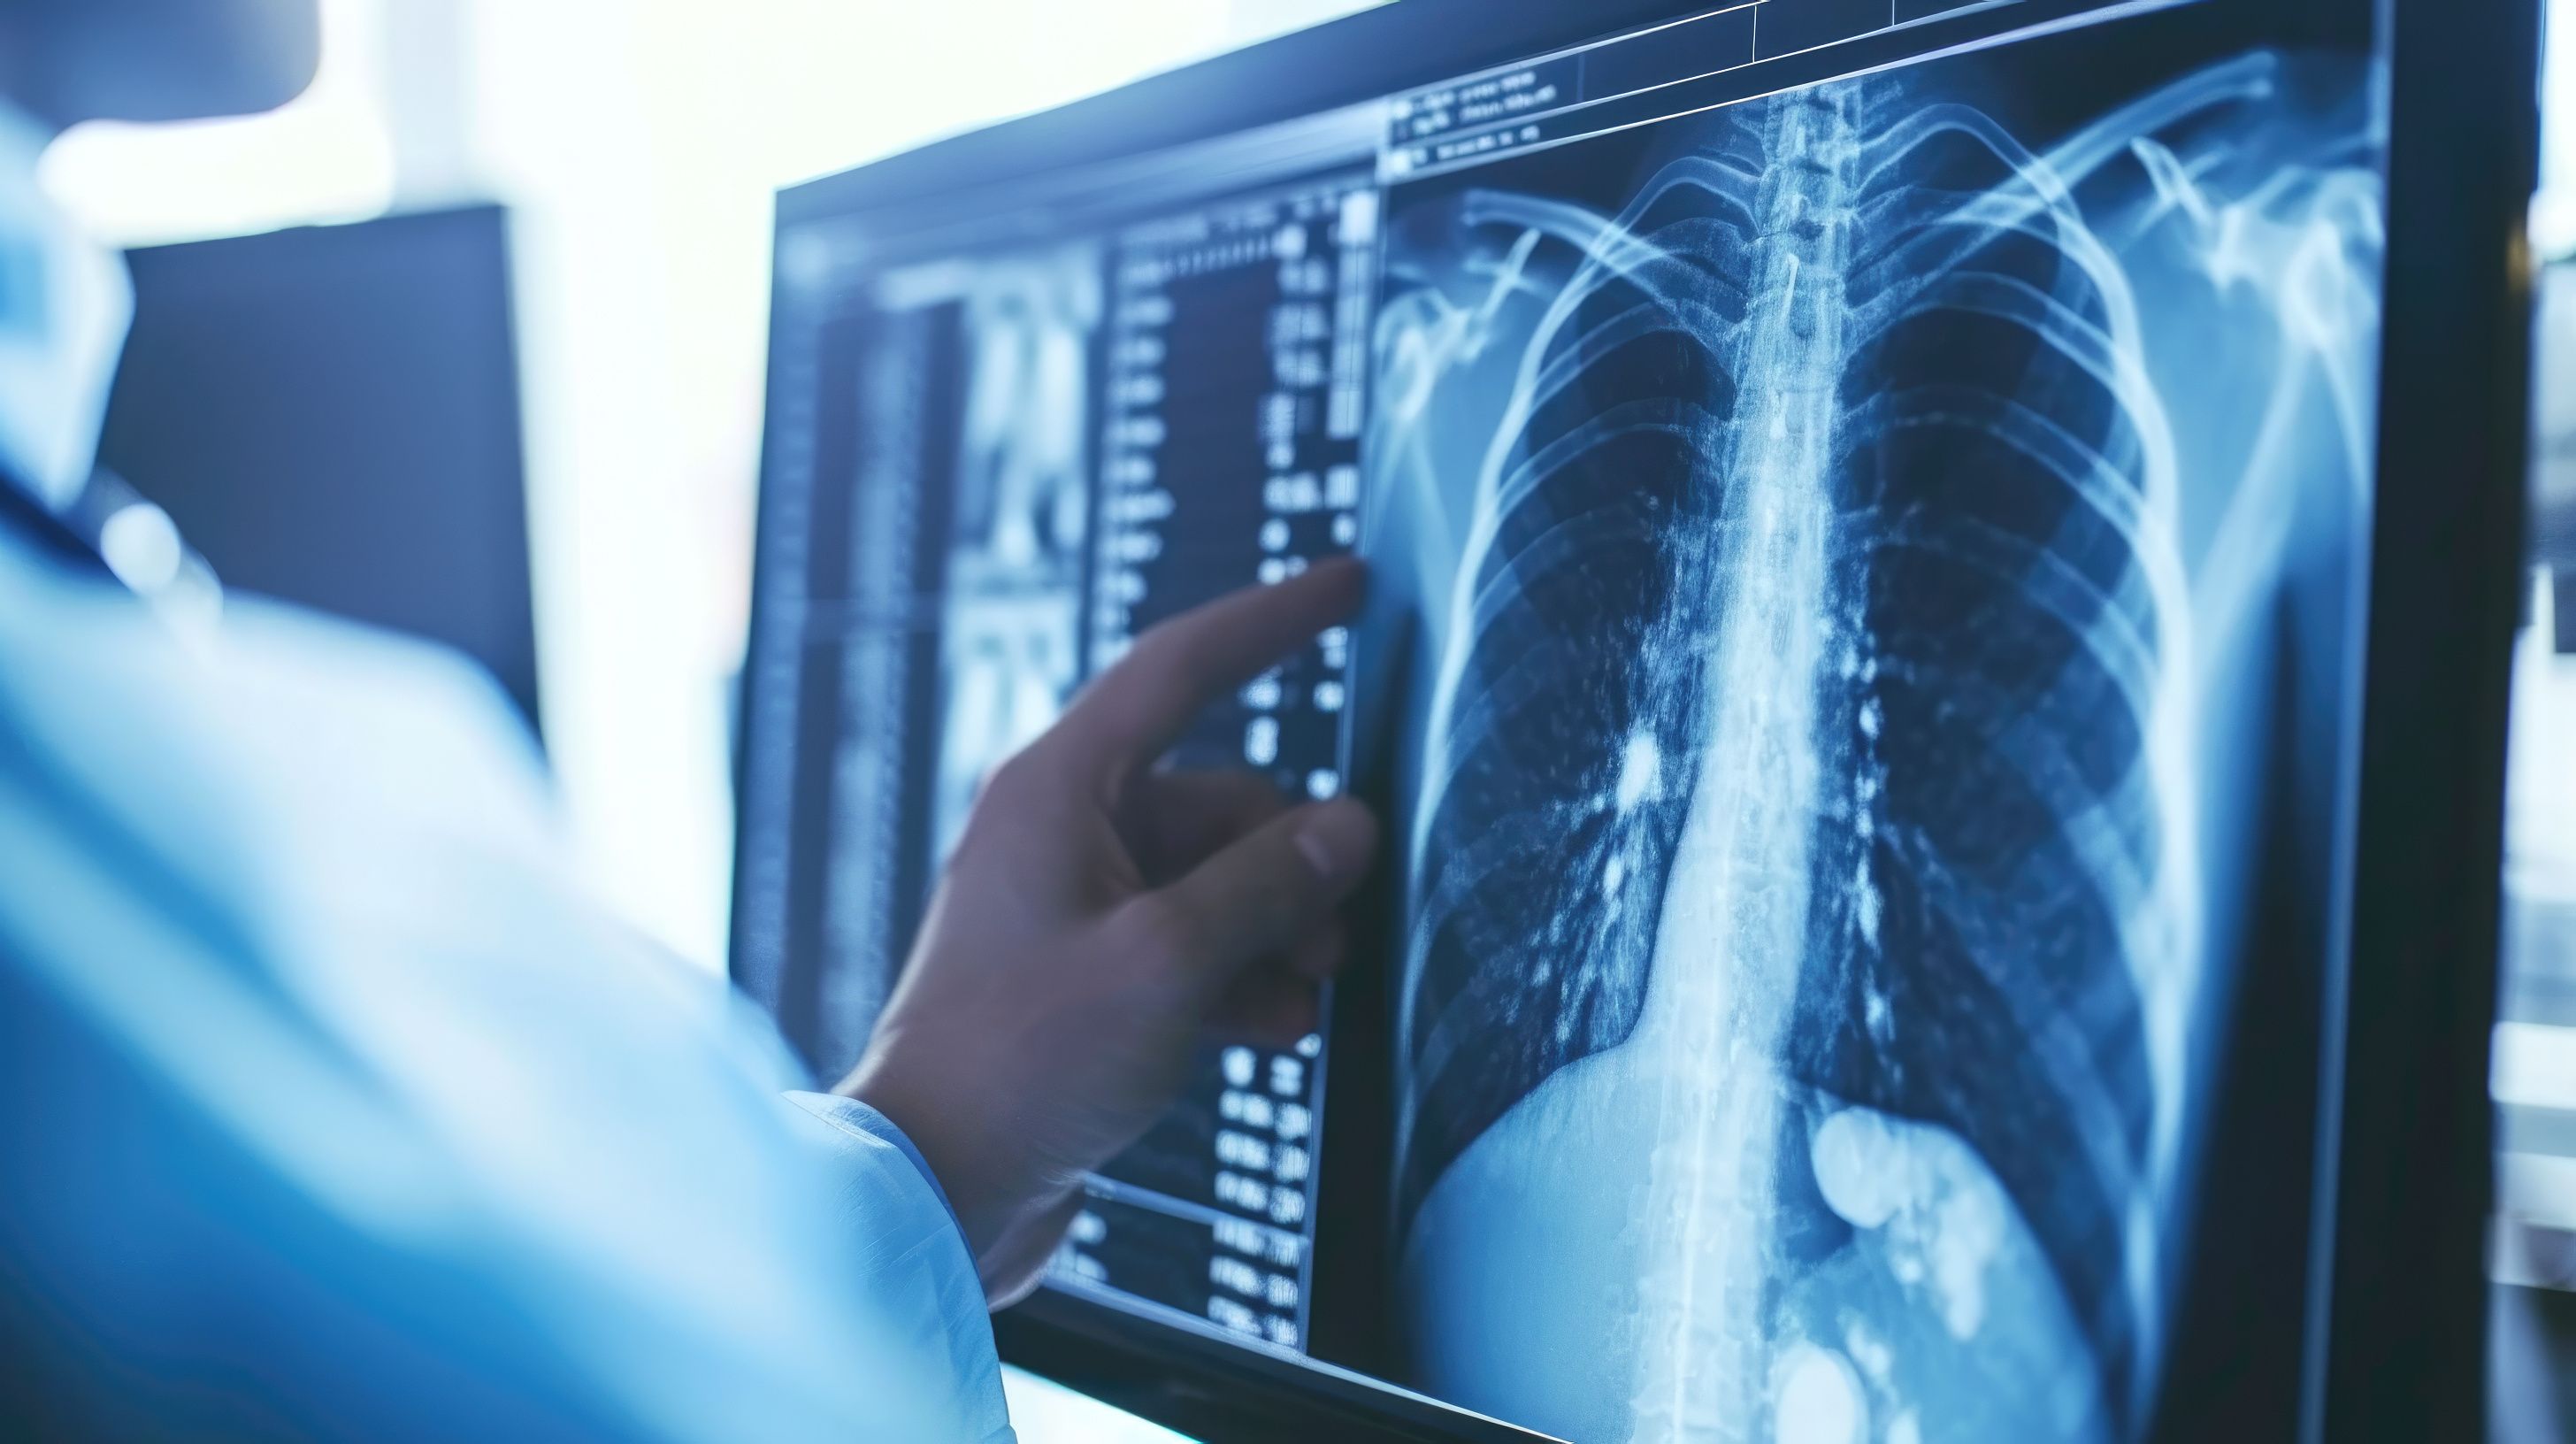

Lung Cancer